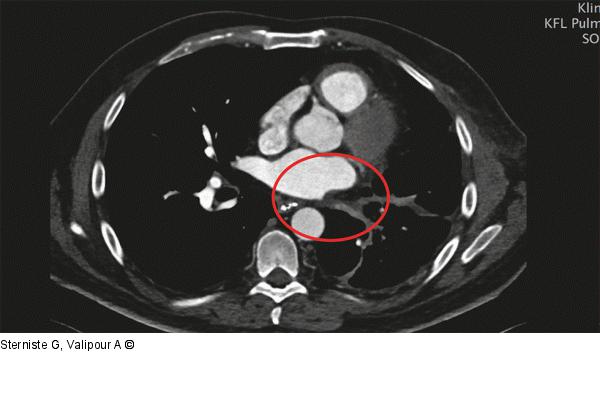

Abbildung 5: Pulmonalvenenstenose Computertomographie: Pulmonalvenenstenose |

Abbildung 5: Pulmonalvenenstenose

Computertomographie: Pulmonalvenenstenose |